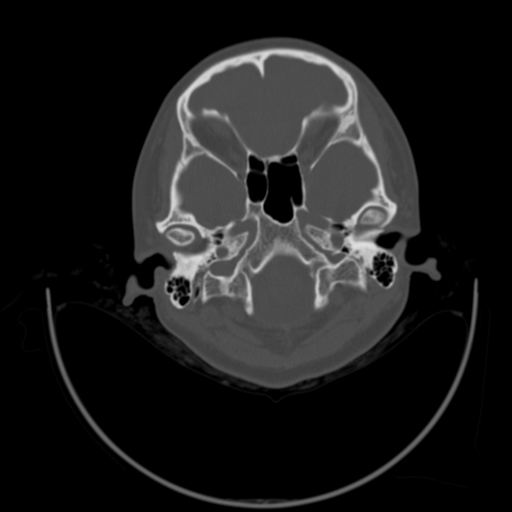

以下是引用随光逐影在2009-3-14 7:58:00的发言:[br]双耳——颞骨ct轴位平扫未见明确异常。